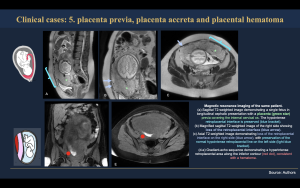

The following section presents representative clinical cases illustrating the spectrum of placental pathologies that may be encountered during magnetic resonance imaging evaluation. These cases highlight key imaging features across the placental compartments, emphasizing normal variants and pathologic findings that are essential to recognize in daily practice. A systematic MRI-based assessment allows accurate differentiation between physiologic changes and abnormal placental invasion, supporting correct diagnosis and optimal clinical management (Figure 19-25).